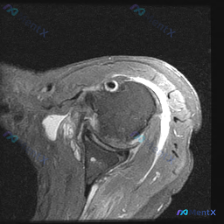

肩关节轴位MRI异常解读:盂唇问题还是肩袖损伤?

图像基本信息:轴位T2加权像(流体敏感序列)

重点影像学表现:

- 肱二头肌长头腱位置正常,腱鞘少量积液

- 肩胛下肌腱连续性尚可,无明显撕裂

- 前、后盂唇形态尚规则,未见明显Bankart损伤等特征

- 肩峰下-三角肌下滑囊有明显高信号带(积液)

- 冈上肌腱/肩袖区域信号不均匀增高,提示可能存在肌腱退变或局部损伤

- 关节软骨、骨性结构无明显异常,关节腔少量积液